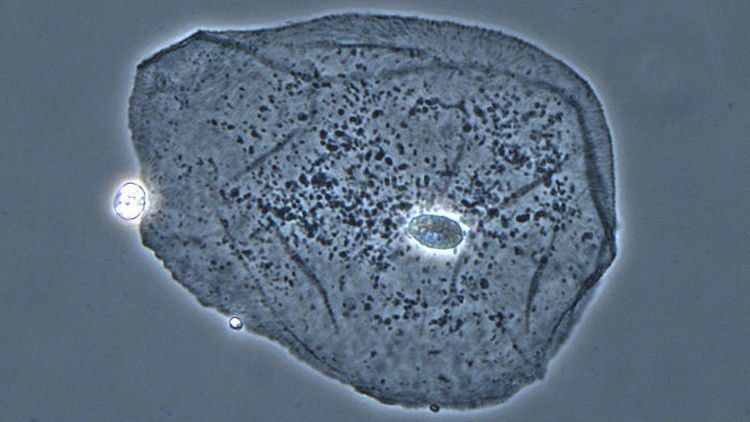

‘Células desmadre’: Explican el mecanismo oculto de la procreación del cáncer

RT Noticias Las células madre no solo ayudan a nuestro organismo a regenerarse o a reparar tejidos. También pueden comenzar a dividirse de forma incontrolable y crear tumores malignos. Eric Werner, un genetista de la Universidad de Oxford, ha propuesto una teoría de redes de desarrollo para describir la actividad de las células madre y […]